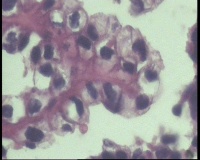

| 一般病史 | 彩超:盆腔可见囊实性回声,囊性为主,大小约5.0x3.7厘米,其内可见分隔回声,部分分隔内回声不纯净,形态欠规整 | ||||

| 标本名称 | 腔镜下右侧卵巢囊肿手术 | ||||

| 大体所见 | 囊壁样组织5.5x5.0厘米,4.5x2.5厘米2块,壁厚0.1-0.2lm,囊壁大部分光滑,局灶见0.7x0.5x0.3厘米淡黄色突起组织,另见淡黄色、肉粉色质软组织2.8厘米一堆。 | ||||